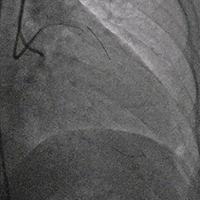

治疗方案(介入治疗·冠脉造影)

LCX近段30%狭窄,OM1 80%狭窄,OM2 90%狭窄,LAD近段100%狭窄,D1高位发出,80%狭窄。

冠脉造影

RCA中段支架内增生 80%,PL 100%。

双侧造影明确LAD开口位置和临近血管关系。